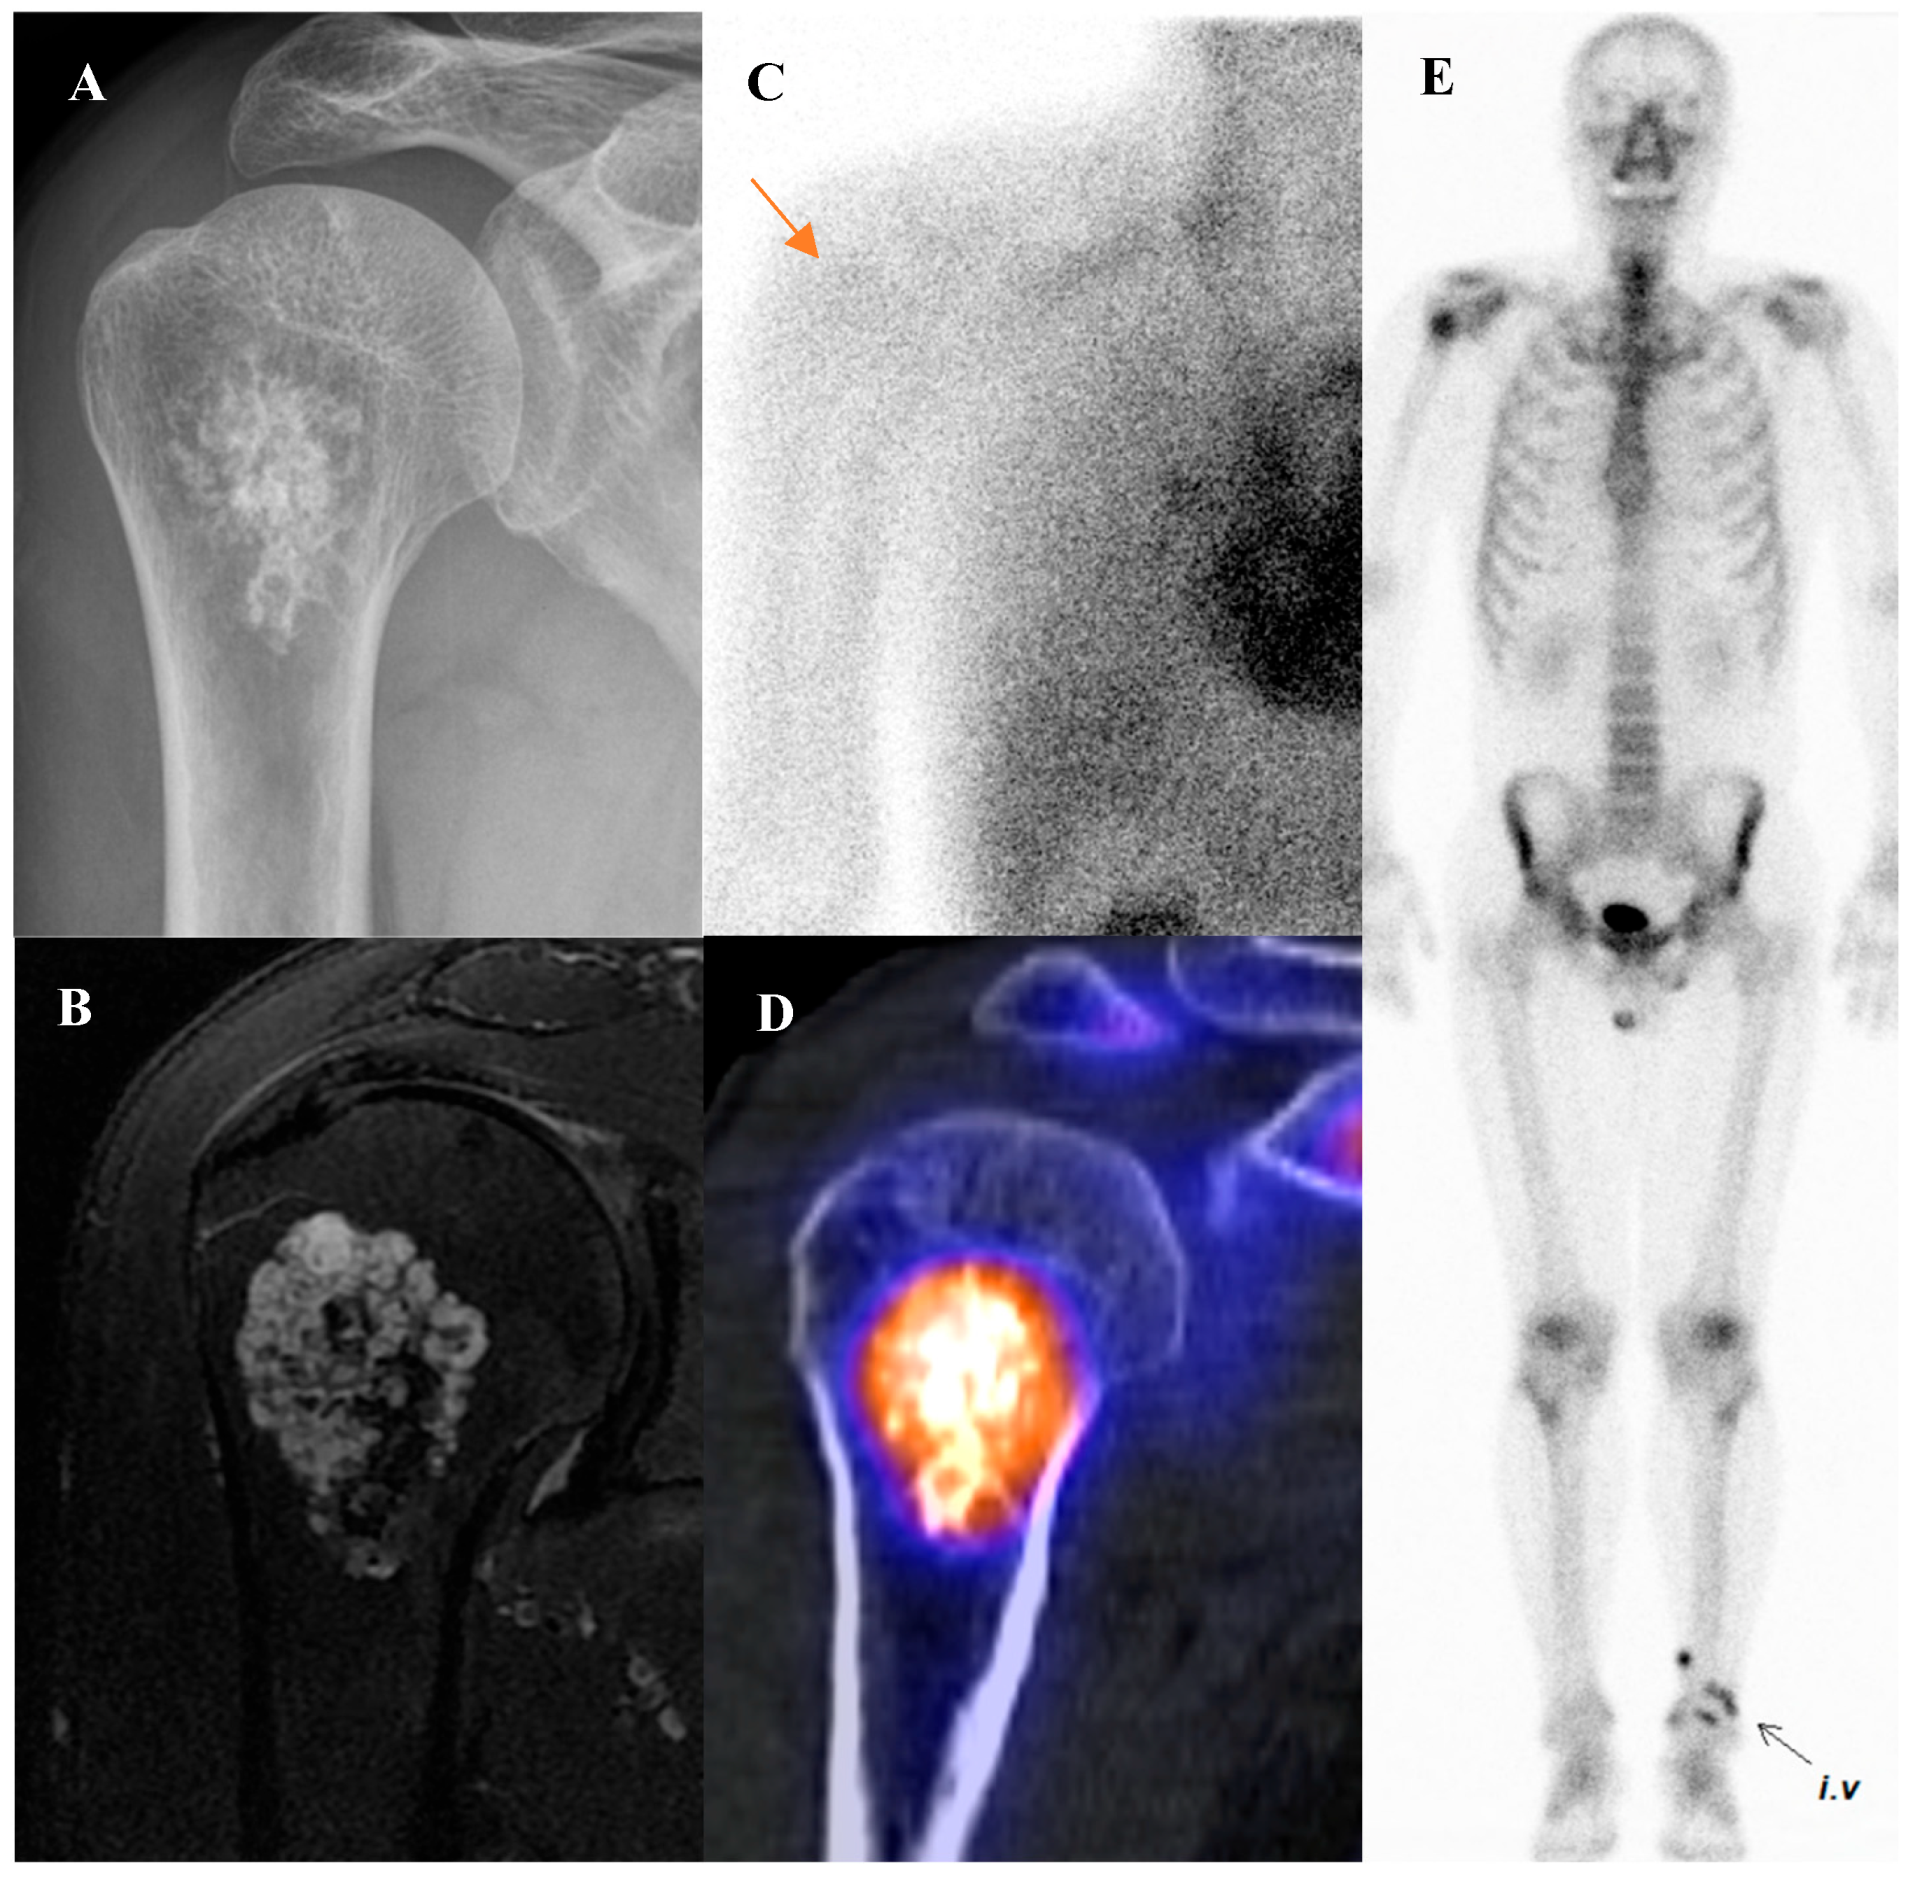

Figure 3 illustrates the spectrum of cartilaginous tumors, from low-grade ACT with mild metabolic activity to high-grade chondrosarcoma with aggressive infiltration and intense uptake, emphasizing the importance of integrating multimodal imaging with histopathology for accurate diagnosis and grading.

Figure 3.

(A–E) A 54-year-old male with atypical cartilaginous tumor (ACT) of the left distal femur. (A) Bone scintigraphy shows increased uptake in the distal metaphysis. (B) Radiograph demonstrates stippled calcifications suggestive of a chondroid tumor. (C) T2-weighted fat-suppressed magnetic resonance imaging (MRI) shows a lobulated intramedullary lesion with heterogeneous signal and equivocal cortical erosion. (D) Bone single-photon emission tomography (SPECT)/computed tomography (CT) demonstrates focal uptake in the distal femur, corresponding to a calcified chondroid mass. (E) [18F]FDG positron emission tomography (PET)/CT shows mild, elongated uptake (SUVmax 2.96) in the lesion with characteristic rings-and-arcs calcification on CT. Surgical excision confirmed ACT. (F–J) A 49-year-old female with high-grade chondrosarcoma of the left acetabulum (F) Bone scintigraphy shows intense uptake. (G) Radiograph demonstrates a geographic radiolucent lesion. (H) T1-weighted fat-suppressed MRI reveals an infiltrative lesion with extraosseous and intra-articular extension, heterogeneous enhancement. (I) SPECT/CT reveals increased uptake in the acetabular region, corresponding to the infiltrative lesion with extraosseous extension. (J) [18F]FDG PET/CT demonstrates intense localized uptake in the left acetabulum with extension into the obturator internus muscle, especially pronounced at the site of extraosseous spread (SUVmax 8.4). Initial biopsy suggested grade I chondrosarcoma; however, wide excision confirmed dedifferentiated chondrosarcoma.